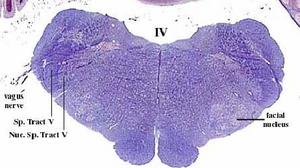

secciones transversales a diferentes niveles del tronco del encéfalo mostrando la localización de los núcleos neuronales eferentes de los nervios craneales

EFERENTES:

somatoeferentes (SE) : inervan músculos esqueléticos

visceroeferentes(VE): parasimpáticos